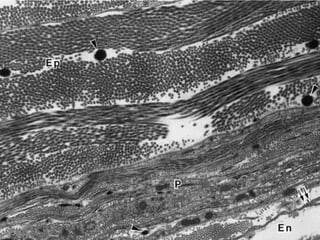

Este documento presenta imágenes microscópicas de diferentes tipos de tejidos y estructuras celulares teñidas con varios métodos histológicos. Incluye fotografías que muestran fibras de colágeno, elásticas y reticulares en diversos órganos, así como membranas basales y células especializadas de órganos como riñones, glándulas mamarias y próstata. El propósito es demostrar la aplicación de técnicas histológicas para visualizar componentes celulares y tej